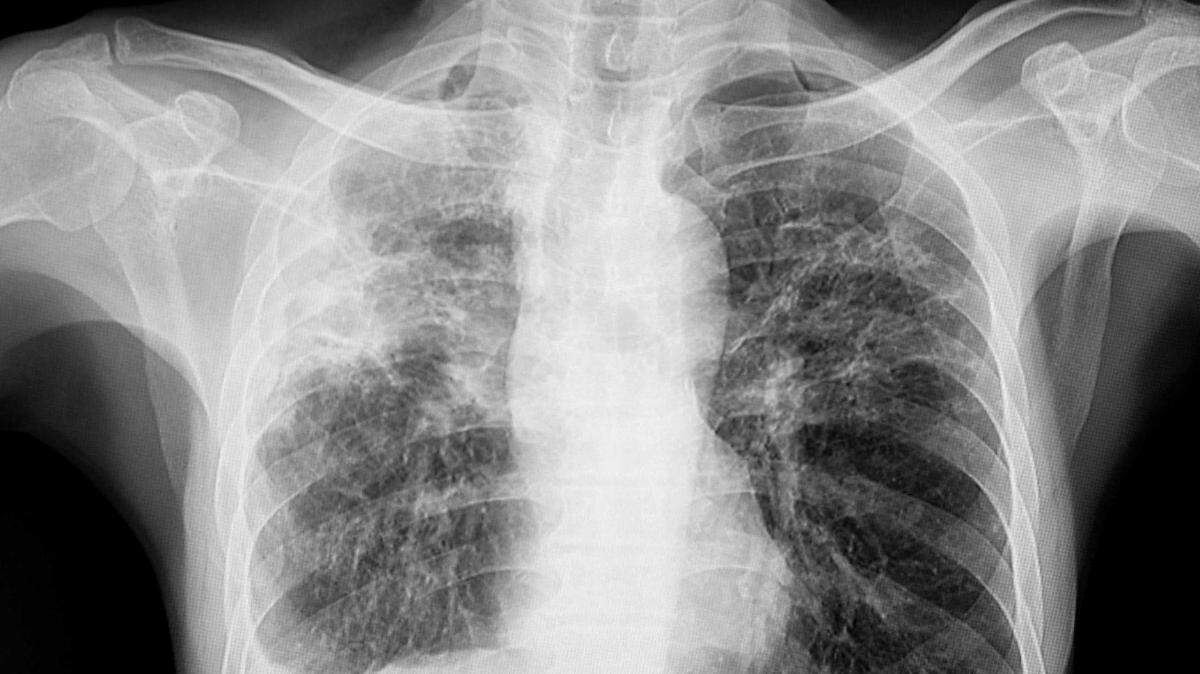

An X-ray shows the lungs of a tuberculosis patient in an undated photo. UC Davis officials said Thursday that they are monitoring an active TB case on campus and have notified individuals who had close contact with the infected person between mid-October and mid-November.

An X-ray shows the lungs of a tuberculosis patient in an undated photo. UC Davis officials said Thursday that they are monitoring an active TB case on campus and have notified individuals who had close contact with the infected person between mid-October and mid-November. Getty Images/iStockphoto